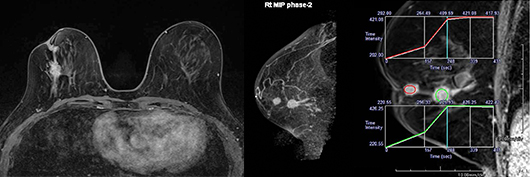

マンモグラフィ

マンモグラフィは乳房の触診検査で、しこりとして触れず超音波検査でも描出されにくい、微細な石灰化を伴う早期の乳がんを発見することに優れています。

この検査では圧迫板と呼ばれる透明な板を備えた乳房専用のX線装置を使用します。乳房をよく引き伸ばしながら圧迫板で挟んで、厚みを薄くしてから撮影することで、乳腺の中に隠れた病変が見つかりやすくなります。また圧迫にはX線被ばくの量を減らす効果もあります。なお、この操作の際、乳房に痛みを伴うことがありますが、1回の撮影に要する圧迫時間は10秒程度です。

当院では2012年7月に富士フィルムメディカル社製AMULET f を導入しました。この装置は直接変換型FPD(フラットパネルディテクタ)と新たな画像処理技術を搭載しており、これまで以上に高精細で低ノイズな画像を安定して医師に提供することが可能となりました。

マンモグラフィ検診施設画像認定を取得

当院は2007年8月よりマンモグラフィ検診精度管理中央委員会の定める検診精度管理の線量・画質基準を満たすマンモグラフィ検診施設として認定されています。

検診マンモグラフィ撮影認定を有する診療放射線技師が撮影を担当し、診断価値の高い画像を提供すると共に日々の精度管理に努めています。また撮影された画像は検診マンモグラフィ読影認定を有する医師によるダブルチェックにて正確な診断がなされています。

マンモグラフィ検診施設画像認定

[造影両乳房撮像例]